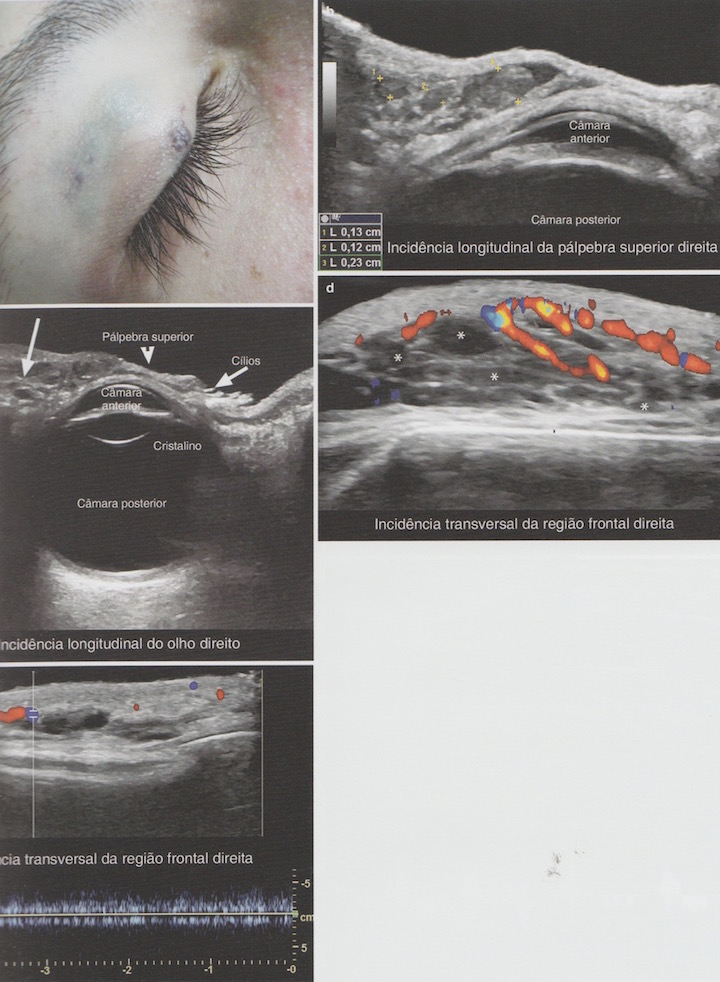

Malformação Vascular Venosa de Baixo Fluxo

Achados:

- Estruturas tubulares anecóicas, tortuosas ou áreas lacunares.

- Fluxo monofásico.